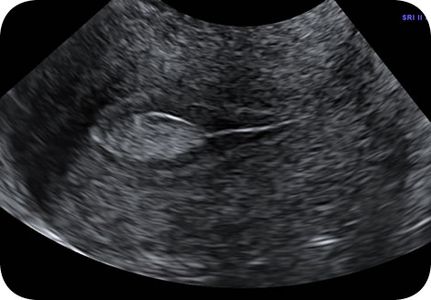

Normal pregnancy is confirmed with an ultrasound seeing a fetus with a heartbeat in the uterus. The earliest we can find these things is 5 ½ weeks after the last period. All normal pregnancies can be confirmed at 7 weeks, based on ultrasound measurements of the fetus. Similarly, the diagnosis of an ectopic pregnancy is based on blood pregnancy tests and an ultrasound.

We can make the diagnosis of an ectopic pregnancy IF: